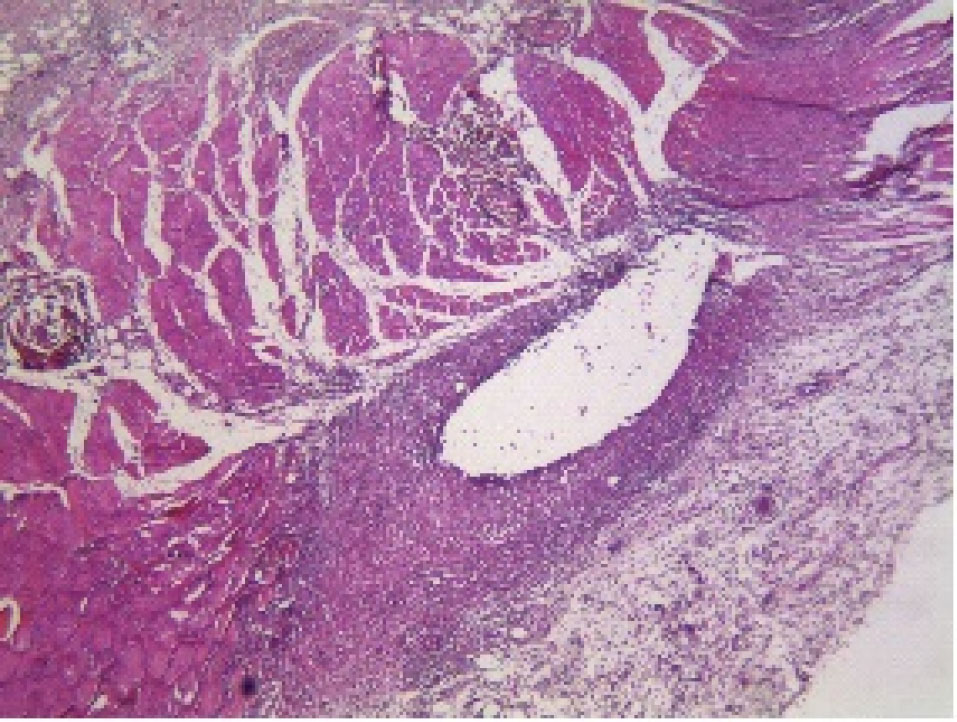

At 30 days after implantation of tubes in the four groups, all of the measured parameters did not show significant difference (P > 0.05). and indicate the histopathological view of granulation tissue at ×40 magnification and giant cells at ×200 magnification.

Figure 1.

Histopathological view of granulation tissue at ×40 magnification (AH-Plus).